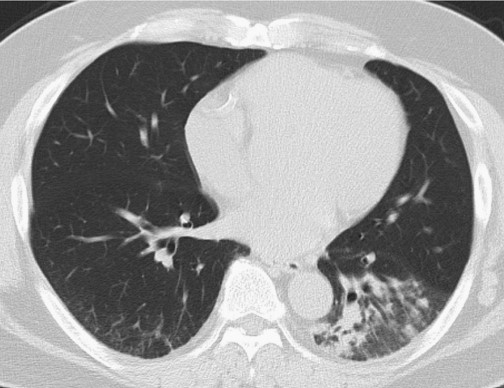

醫(yī)生試圖進行腰椎穿刺,但因患者肥胖,手術終止。因癥狀較輕,給予患者每日小劑量氟康唑(100 mg po)治療,若效果不明顯則增加劑量。1個月后隨訪,患者表示咳嗽改善,CT顯示實變陰影明顯改善(圖3)。

圖3 高分辨率CT掃描顯示,1個月后患者左肺下葉實變改善